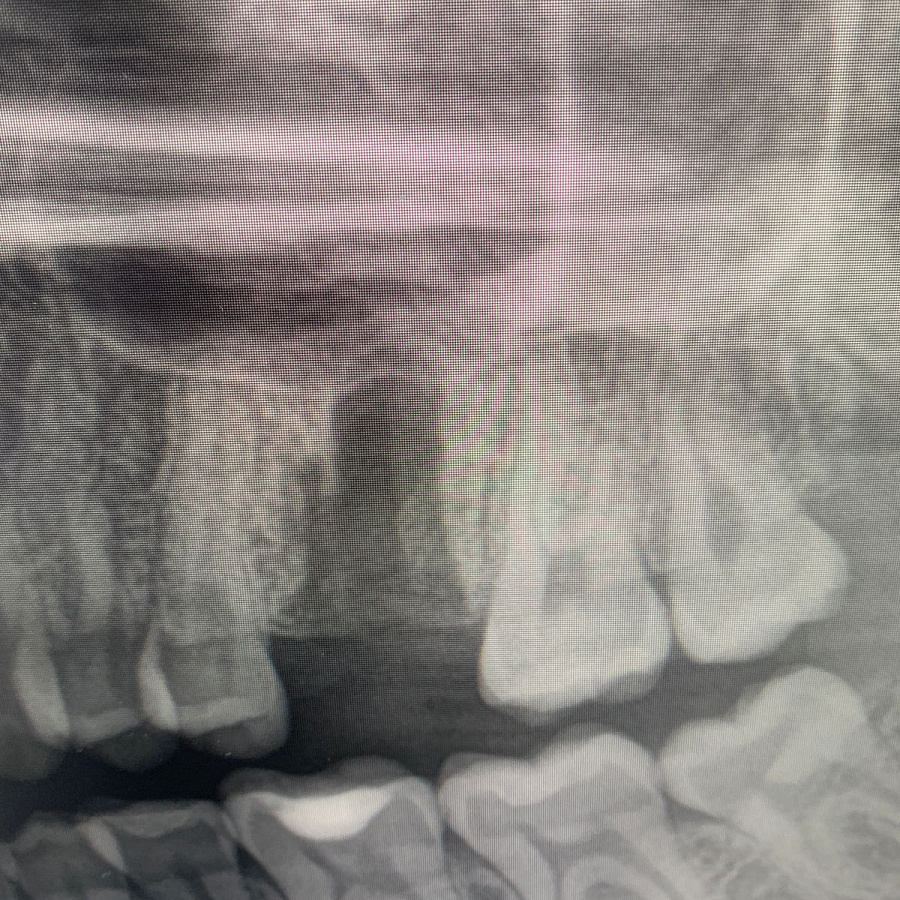

После удаления таких зубов и извлечения кисты, в кости остаётся большой дефект. Поэтому сделать одномоментную имплантацию зуба, т.е. удаление и имплантацию за один приём невозможно. В таких случаях необходимы дополнительные хирургические манипуляции по подсадке искусственной кости, чтобы сохранить объём костной ткани для последующего протезирования.

Через 6 месяцев после подсадки кости - контрольный снимок и установка зубного имплантата.